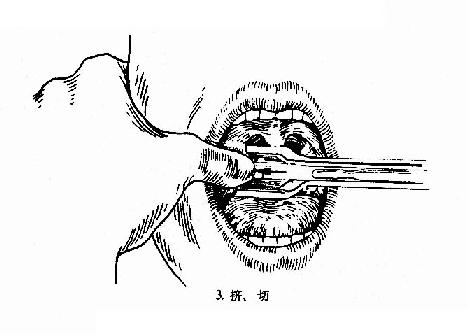

(二)挤切法(guillotine method)(图6-3):

2.操作:病人取仰卧或坐位,助手将其头部固定,置入开口器后,手术者以压舌板压舌,暴露扁桃体下极,右手持挤切刀,从扁桃体下极套入,再转动刀环,使其位于扁桃体和咽腭弓之间,将扁桃体后面及上极套入,并向舌腭弓方向提起,这时扁桃体在舌腭弓下隆起成一“包块”,即用左手拇指或食指将“包块”挤压入环内,随即收紧刀柄,推动刀杆前进,使刀片切入刀环的尽端,以迅速有力的扭转及提拔动作切下扁桃体。以同法切除对侧扁桃体。助手迅速将患者头部侧转,使其将血吐出。止血方法同剥离法。

图6-3 扁桃体挤切术